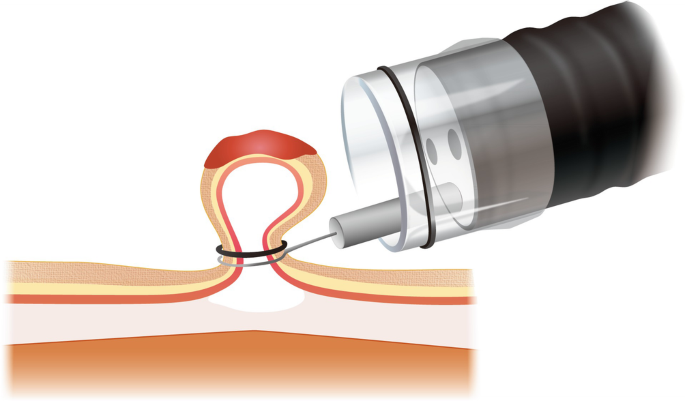

These are life-saving procedures often performed in emergency settings or as part of a regular de-varicealization program.